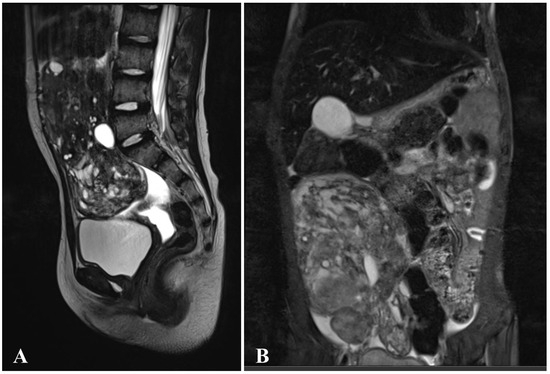

| ID8 Female 15y.o. | Macrocephaly | Papillary thyroid cancer (11) | Macrosomia (0), ventricular septal defect, papillomas in the right axilla, and on the left hand | Germ cell tumor of the right ovary (7) |

| ID11 Female, 14y.o. | Macrocephaly | Multinodular goiter (10) | Macrosomia (0) | Germ cell tumor of the right ovary (4) |

| ID12 Female 10y.o. | Macrocephaly | Fibrolipoma of suprascapular region (4 months) | Macrosomia (0), scaphocephaly | Germ cell tumor of the left ovary (8) |